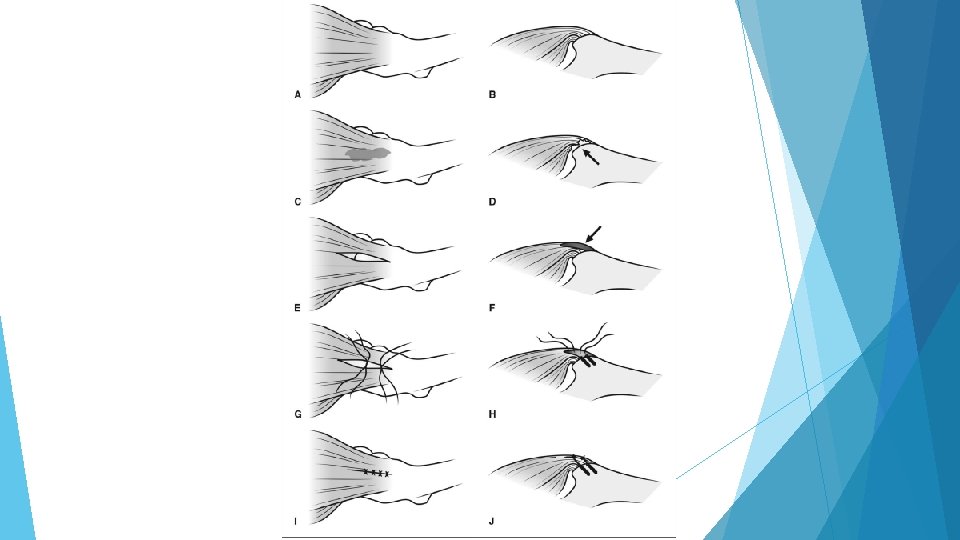

Abductor Tears The Rotator Cuff of the Hip Coaches, Active Parents, Teachers, and other active adults (typically >50 s)

Abductor Anatomy

Abductor repair surgery